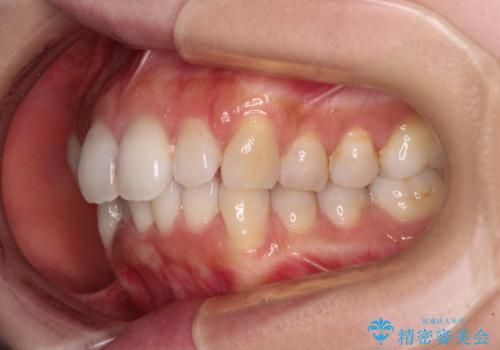

- デコボコと飛び出している前歯を気にして来院された患者様です。

歯列としてはインビザラインでもワイヤー矯正でも対応できるものでしたが、奥歯の咬み合わせを見た時に上顎がやや前方にあり、インビザライン単独では時間のかかってしまう可能性があるため、補助装置を治療当初に使用することで、インビザラインによる治療をスムーズに行えるように計画しました。

インビザラインは得意・不得意の差がはっきりとしているため、補助装置やワイヤー装置などをうまく活用することで、治療期間を短縮するとともに、より理想的な仕上がりを達成することができます。